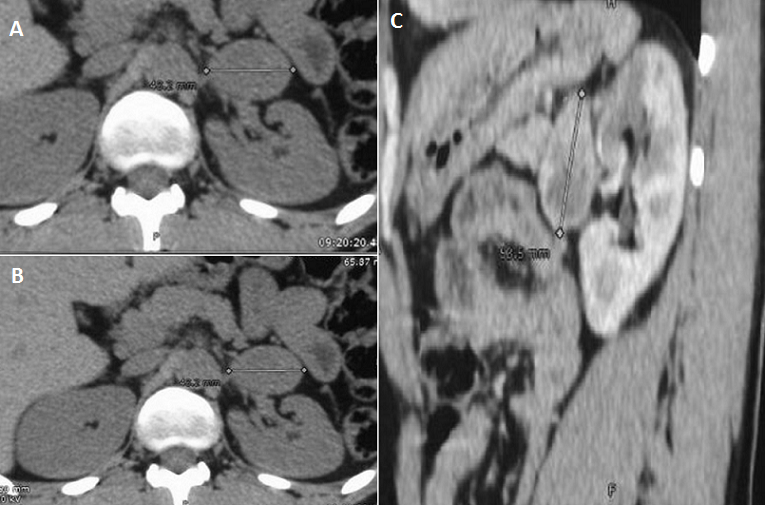

Le scanner ou l’imagerie par résonance magnétique (IRM) sont les examens de première intention afin de localiser une tumeur surrénalienne. L’imagerie doit d’abord explorer les glandes surrénales avec étude des deux jambages de la glande et la recherche de processus tumoral. En effet, pour préciser si la tumeur est d’origine surrénalienne ou pas, il suffit d’étudier ses rapports et son contact avec la glande; en présence d’une tumeur de l’aire surrénalienne refoulant la surrénale, elle est plutôt extrasurrénalienne, et si elle la déforme, la tumeur peut être considérée à priori comme étant d’origine surrénalienne. Nous rapportons le cas d’un patient de 27 ans, ayant comme antécédent un accident vasculaire cérébral ischémique remontant à un an faisant suite à un pic hypertensif. Le diagnostic d’hypertension artérielle a été depuis lors posé. Devant l’âge jeune du patient, un bilan d’hypertension artérielle secondaire a été réalisé, il avait objectivé une élévation significative des dérivés méthoxylés urinaires et du cortisol libre urinaire. Un scanner surrénalien a été, par la suite réalisé, il avait montré des surrénales d’aspect normal avec présence d’une lésion pré rénale gauche au contact du jambage externe de la surrénale mesurant 43 mm ; elle est de forme ovalaire bien limitée spontanément hypodense (A), cette masse se réhausse d’une façon intense et hétérogène après injection de produit de contraste (B). Les coupes sagittales avaient bien montré la localisation pré-rénale de la masse dont le grand axe sagittal est de 54 mm (C)